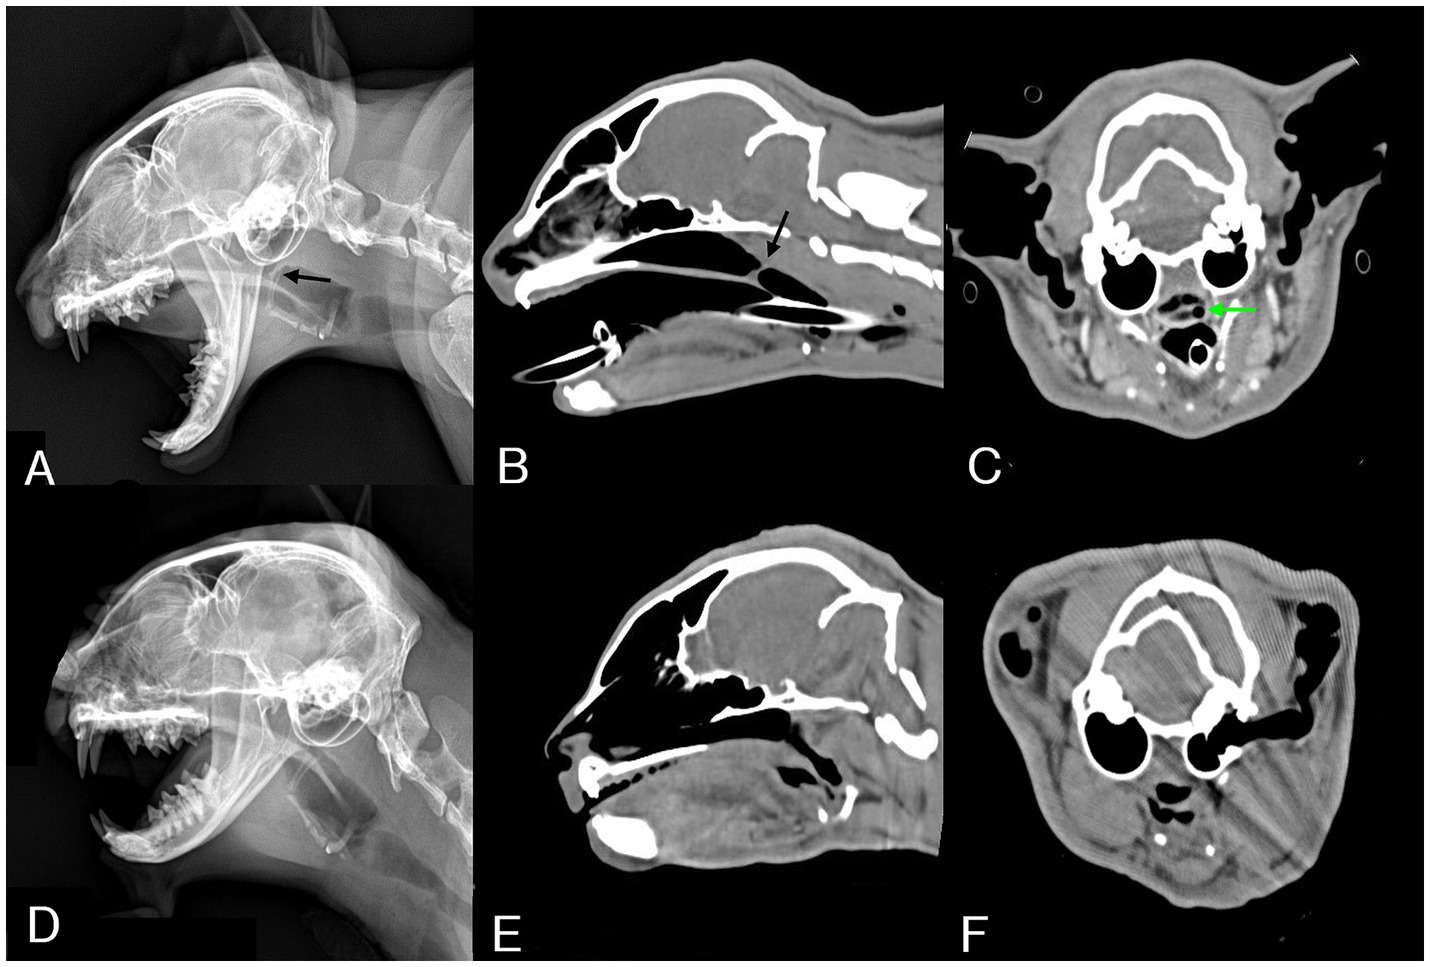

Se obtuvieron radiografías laterales de la cavidad torácica, cabeza y cuello. La radiografía reveló una estructura delgada en forma de banda de opacidad de tejidos blandos en la región nasofaríngea, 15 mm rostral hasta el final del paladar blando (Figura 1A). Además, la reconstrucción sagital de la TC confirmó la presencia de una estructura membranosa de 1 mm de espesor en la cara dorsal del paladar blando (Figura 1B). Las mediciones de las imágenes tomográficas computarizadas utilizadas para la planificación del tratamiento incluyeron una distancia de 75 mm desde el plano nasal hasta el área estenótica (Figura 1B), con un ancho de 11 mm de la nasofaringe frente al área estenótica, y el ancho más estrecho del área estenótica (2,5 mm) desviándose hacia la izquierda desde el centro (Figura 1C). No se observaron otras anomalías anatómicas o patológicas.

El gato fue reevaluado 4 semanas después de la última aplicación de MMC. La radiografía lateral de la cabeza del cráneo y la tomografía computarizada revelaron la desaparición de la estructura membranosa (Figuras 1D,E). Además, se confirmó la permeabilidad desde la nasofaringe hasta la cavidad oral (Figura 1E), con dilatación del área estrechada (Figura 1F).